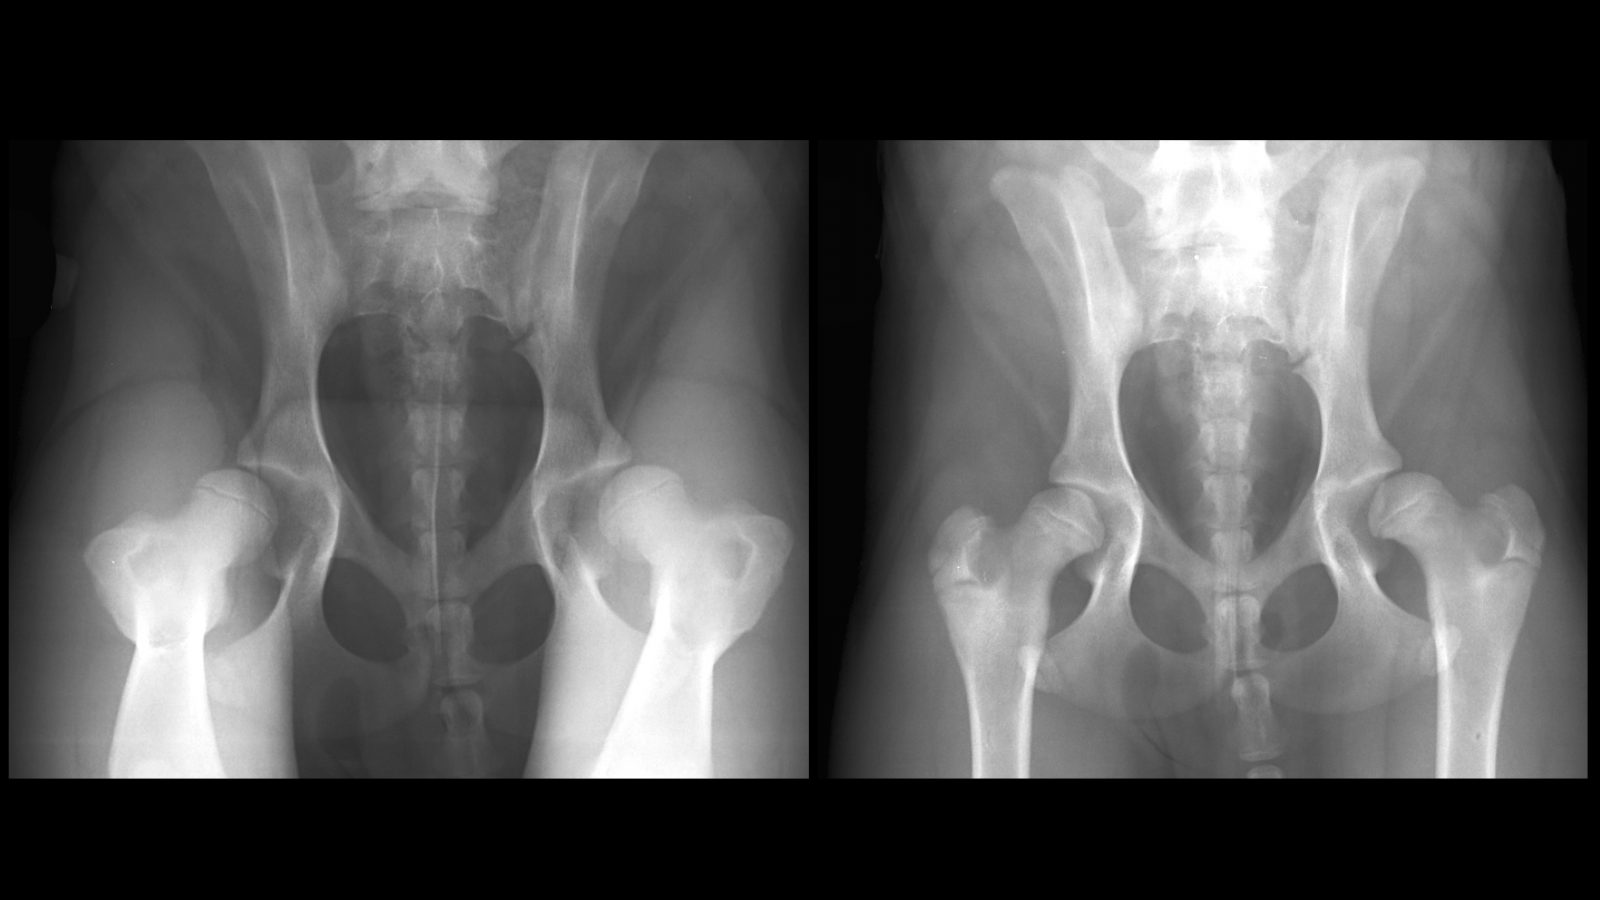

Can A Vet Feel Hip Dysplasia. while a hip dysplasia diagnosis can be devastating news, it doesn’t mean your dog is condemned to a. how long can a dog live with hip dysplasia? With proper surgical and medical management, a dog with hip dysplasia can. Hip dysplasia results from a combination of genetic makeup and environmental factors. if your dog has hip dysplasia, you might notice signs including: Can hip dysplasia be treated? it’s important to keep an eye on them and take them to a vet if you see them displaying any of the above symptoms. to help you identify canine hip dysplasia in your dog, it helps to have some background information and know the. hip dysplasia is a common condition that affects a dog’s joints and ability to get around without pain. your veterinarian will likely extend the dog's hind leg backward to check for pain as hip dysplasia causes pain on. this results in a loosening or laxity within the hip. if you suspect your dog has hip dysplasia, the first step is to consult your veterinarian. as with any medical condition, a diagnosis of hip dysplasia must come from a veterinary professional. hip dysplasia is an inherited condition resulting from an improperly formed hip joint. ip dysplasia is one of the most common orthopedic conditions in dogs.

this results in a loosening or laxity within the hip. hip dysplasia is a painful condition that can affect dogs of any breed. Clinical signs and palpable joint. Limping or lameness weakness or pain in their hind. They can provide valuable insights by observing your dog’s. if your pooch is showing signs of hip dysplasia such as pain or discomfort when exercising, it’s important to get. hip dysplasia can be caused by a variety of factors including: Because the joint is loose, the dog's leg. your veterinarian will likely extend the dog's hind leg backward to check for pain as hip dysplasia causes pain on. hip dysplasia is an inherited condition resulting from an improperly formed hip joint.

Can A Vet Feel Hip Dysplasia hip dysplasia is an inherited condition resulting from an improperly formed hip joint. if you suspect your dog has hip dysplasia, the first step is to consult your veterinarian. They may refer you to a specialist vet to. Over time, this causes wear and tear to the cartilage and even the bone itself. if your dog has hip dysplasia, you might notice signs including: Hip dysplasia results from a combination of genetic makeup and environmental factors. Because the joint is loose, the dog's leg. to help you identify canine hip dysplasia in your dog, it helps to have some background information and know the. your veterinarian can discuss medical and surgical options with you if your dog has hip dysplasia. ip dysplasia is one of the most common orthopedic conditions in dogs. it’s important to keep an eye on them and take them to a vet if you see them displaying any of the above symptoms. this results in a loosening or laxity within the hip. hip dysplasia is a painful condition that can affect dogs of any breed. while a hip dysplasia diagnosis can be devastating news, it doesn’t mean your dog is condemned to a. your veterinarian will likely extend the dog's hind leg backward to check for pain as hip dysplasia causes pain on. hip dysplasia can be caused by a variety of factors including: